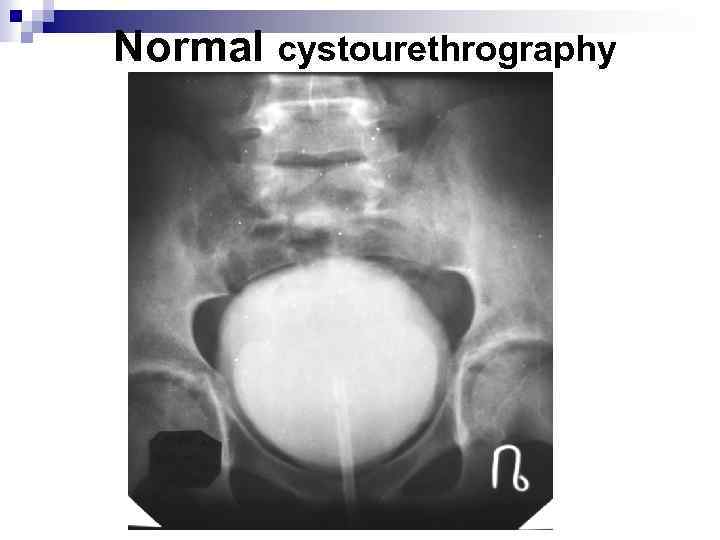

Normal cystourethrography

Normal cystourethrography